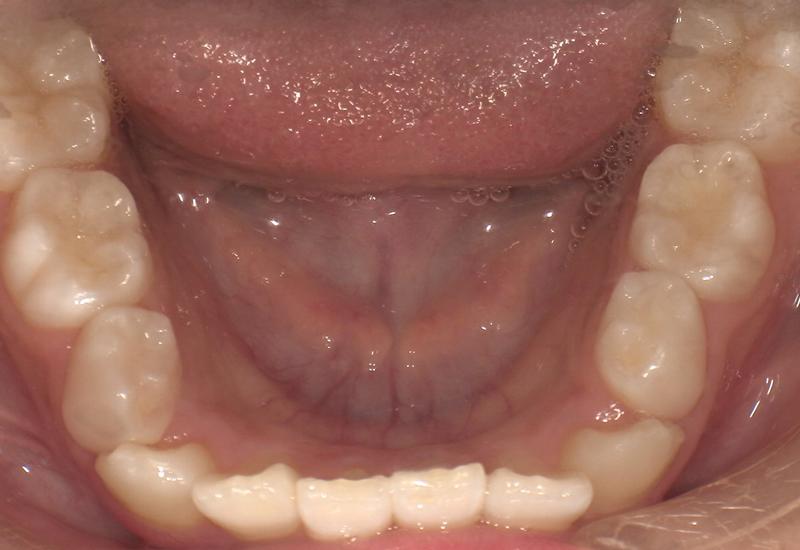

症例② シェイプメモリーアライナーによる混合歯列期の矯正

治療期間 6ヶ月

治療時の年齢/性別 10歳 / 女性

かかった治療費 440,000円

治療方法 シェイプメモリーアライナー

注意点・リスク 今、現在萌えてきている永久歯を動かす為、なるべく早く治療を終了させる